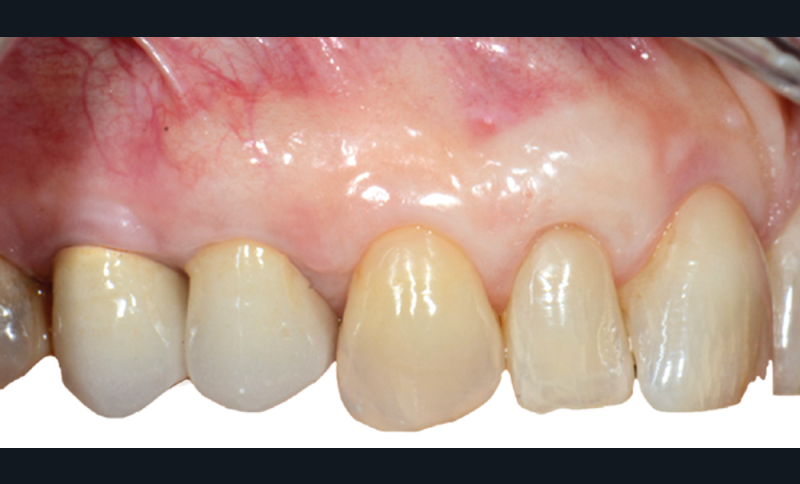

Cette technique, sans greffon de conjonctif associé, permet un taux de recouvrement complet de 80 %. La préservation de l’épaisseur du lambeau et la présence du périoste semble jouer un rôle fondamental dans l’obtention du recouvrement complet.